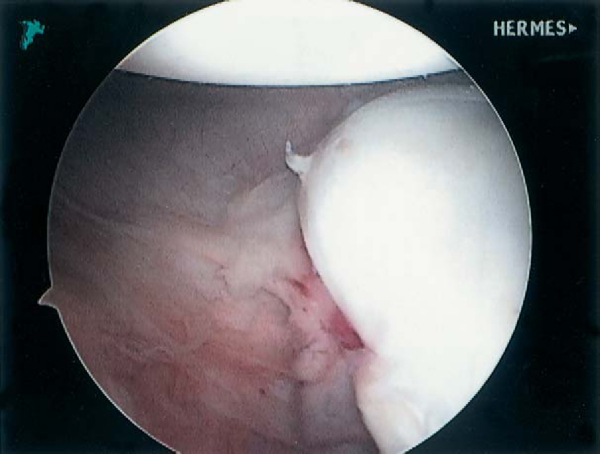

Commonly, the AIGHL is released and mobilized with care from both the glenoid and the underlying subscapularis with the use of an electrocautery device. If an anterior labroligamentous periosteal sleeve avulsion (ALPSA) lesion is encountered (

Fig. 4-4

), the periosteum should be incised to release the AIGHL from the anterior glenoid (

Fig. 4-5